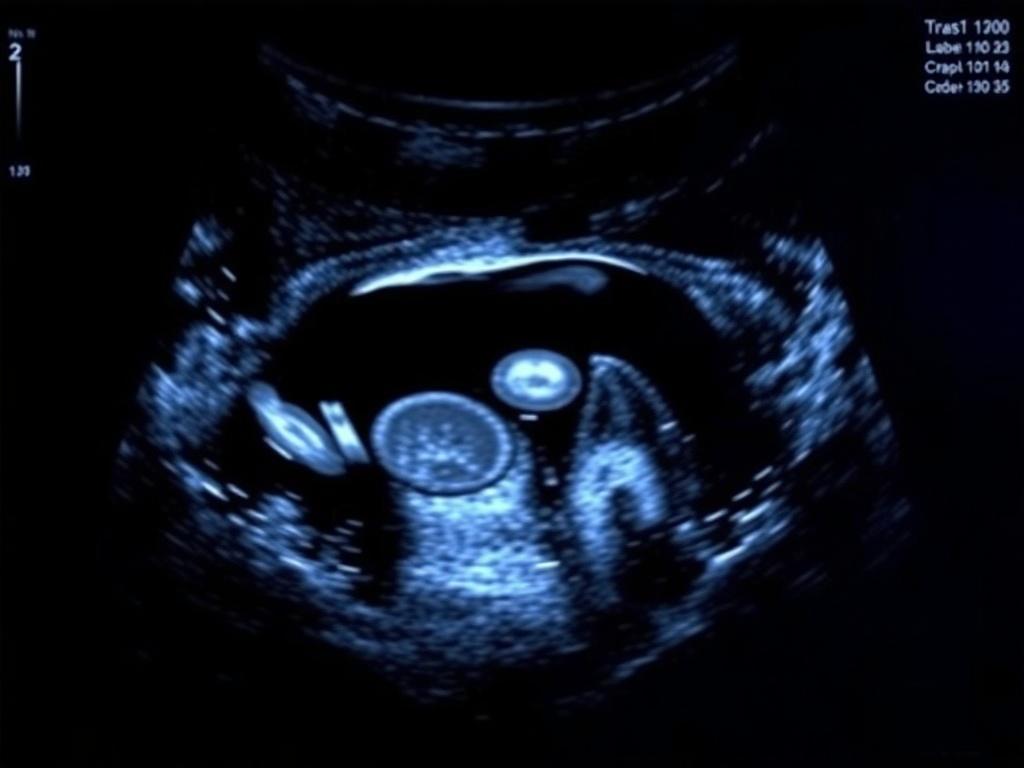

К наступлению климакса многие женщины относятся настороженно: новые симптомы, резкие перемены в самочувствии, тревожные мысли о здоровье. Но именно в этот период ультразвуковое исследование органов малого таза становится одним из самых практичных и безопасных инструментов, позволяющих увидеть реальные изменения внутри организма и вовремя заметить тревожные сигналы. Разберёмся, зачем оно нужно, что именно можно увидеть на УЗИ и как правильно подготовиться к обследованию, чтобы результат был максимально информативным.

Ультразвуковое исследование даёт изображение нескольких важных структур и зон. В общей картине нужно увидеть несколько ключевых моментов, чтобы оценить состояние органов малого таза в период климакса.

— Матка: размер, форма, контур, положение. УЗИ позволяет определить наличие деформаций, изменений плотности миометрия, признаки аденомиоза, а также оценить состояние шейки матки.

— Эндометрий: толщина и структура слизистой оболочки полости матки. В постменопаузе эндометрий обычно тонкий; утолщение может быть признаком гиперплазии или рака и требует дополнительной оценки.

— Яичники: размер, наличие тканей, кисты или поликистозность. В климакс яичники часто уменьшаются в объёме и их функция снижается; однако новообразования требуют внимания.

— Аденнокинезия и миомы: размер, число и локализация узлов, их влияние на полость матки. Миомы могут давать симптомы давления, боли или аномальное кровотечение.

— Задняя стенка таза и соседние структуры: мочевой пузырь, петли кишечника и связь с тазовым дном — иногда изменения в этих зонах влияют на общее самочувствие женщины.

— Кисты и образования в придатках: иногда на УЗИ удаётся обнаружить кисты или воспалительные очаги, что особенно важно для своевременного лечения.